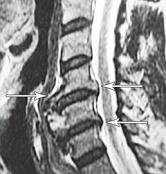

На МРТ № 40 наблюдается типичный пример развития стеноза второго типа в шейном отделе позвоночника. И аналогичная картина, только, в поясничном отделе позвоночника, отображена на МРТ № 41 Стеноз Стеноз позвоночного канала встречается довольно часто, во всяком случае в моей практике. В данной книге я уже упоминал о том, что стеноз спинномозгового канала (то есть его сужение) может вызывать серьёзные осложнения при течении таких заболеваний, как например, грыжи межпозвонкового диска. Для лучшего понимания происходящих процессов давайте в общих чертах рассмотрим, что такое стеноз и чем он опасен. Итак, стеноз — это врождённое или приобретённое аномальное сужение просвета какого-либо полого органа (пищевода, кишечника, кровеносного сосуда и др.) или отверстия между полостями (например, при пороках сердца). Стеноз позвоночного канала характеризуется его патологическим сужением. Исходя из анатомо-физиологических особенностей позвоночного канала, который является вместилищем и в тоже время охранным футляром для спинного мозга, даже незначительное его сужение может оказаться фатальным для спинного мозга. К примеру, при развитии абсолютного стеноза позвоночника спинной мозг может быть компримирован (сжат) вместе с артериями. В свою очередь это неизбежно ведёт к развитию ишемии (от греч. ischo — «задерживаю, останавливаю» и haima — «кровь»; уменьшение кровоснабжения участка тела, органа или ткани вследствие ослабления или прекращения притока к нему артериальной крови) тех участков спинного мозга, где блокировано кровоснабжение сдавленными сосудами. Ещё в конце XIX века, а точнее в 1880 году, в своей работе М. Литтен отметил, что спинной мозг более чувствителен к ишемическим повреждениям и недостатку кислорода, чем другие ткани организма. А вот отечественному невропатологу, ученику В. М. Бехтерева и одному из первых нейрохирургов, Л. М. Пуссепу в 1902 году удалось в эксперименте на животных показать, что даже непродолжительная ишемия спинного мозга влечёт за собой некроз (отмирание) нервных клеток передних рогов спинного мозга. Если добавить к этому ещё и неизбежное нарушение ликвородинамики и развития (вследствие сдавления оболочек спинного мозга) эпидурита и арахноидита, то возникновение болевых, корешковых и сосудистых синдромов (в виде миелоишемии, радикулоишемии или миелорадикулоишемии) становятся вполне объяснимыми и понятными. Исходя из классификации, предложенной доктором I. Stephen, которой пользуется большинство авторов в своих работах, стеноз позвоночного канала позвоночника, как я уже упоминал, бывает двух типов. Тип первый — врождённый, или как его ещё называют идиопатический, то есть беспричинный (неизвестного, неясного происхождения). Второй тип — приобретённый, возникший вследствие дегенеративно-дистрофических процессов в позвоночнике, посттравматический или обусловленный другими причинами, которые привели к стенозированию (сужению) позвоночного канала. Например, грыжа межпозвонкового диска даже центральной локализации, имеющая размер всего 6 мм в дорсальном направлении в поясничном отделе позвоночника с сагиттальным размером спинномозгового канала в 15 мм приводит к формированию абсолютного стеноза второго типа (приобретённого) и может вызвать серьёзные осложнения. А при стенозе первого типа (врождённого, см. МРТ № 43), к примеру с сагиттальным размером спинномозгового канала в поясничном отделе 12 мм, даже трёхмиллиметровая протрузия межпозвонкового диска может привести к развитию слабости в ногах, мышечной атрофии или, как описывал данные состояния Dejerine ещё в 1911 г., «перемежающейся хромоте спинальной природы». |